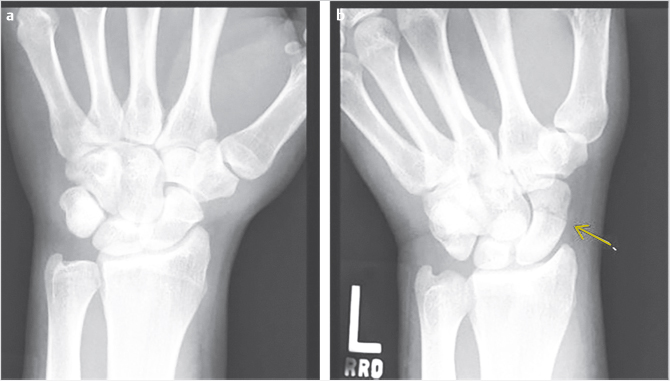

In the radiographic evaluation of hand fractures, plain radiographs are the mainstay of diagnosis. All hand injuries should be evaluated with anteroposterior (AP), lateral, and oblique radiographs. These three views are essential for visualizing the small bones in the hand to best characterize, and avoid missing, any fractures. In addition, it is best to order radiographs as specific to the injury as possible for the best view. For example, if the small finger has a deformity and a fracture is suspected, a three-view series of the small finger will yield higher quality images than a three-view series of the hand. This is because the sharpest images are obtained when the X-ray beam is centered over the area of interest; for example, hand series X-rays center the beam over the middle finger metacarpal which contrasts with dedicated finger series which center over the proximal phalanx. As a result, the AP image of a hand will capture the small finger slightly supinated potentially obscuring subtle fractures (Fig. 24‑2). In some injury patterns, additional radiograph views are useful, such as hook of the hamate view, navicular view, Robert’s view for a true AP view of the thumb, and dynamic studies such as the clenched fist view (Fig. 24‑3). 1 , 2 Computed tomography (CT) imaging is required only occasionally for fracture evaluation. Indications for CT imaging are primarily for operative planning in highly comminuted, intra-articular fractures. Magnetic resonance imaging is likewise rarely required for hand fractures, indicated mainly for detecting occult scaphoid fractures or early avascular necrosis such as in Kienbock’s disease. 2 While ultrasound imaging can be useful for soft-tissue hand injuries, it does not have utility in evaluating fractures.

When reading the radiographs, the treating physician should be able to accurately diagnose and describe the type of fracture sustained. This not only allows for determination of appropriate treatment but also ensures accurate and efficient communication with other physicians. Possible fracture patterns include transverse, oblique, spiral, and comminuted (Fig. 24‑4). Fractures are described by identifying the type of fracture, whether it is open or closed, commenting on the degree of comminution if present, the presence and direction of fracture fragment angulation, whether the fracture is apex-volar or apex-dorsal, whether there is any shortening or segmental loss of the overall bone length, measurement of any step-off of the fracture fragments, description of any rotational deformity, quantifying any articular surface involvement, and whether there is any associated joint dislocation (Fig. 24‑5).